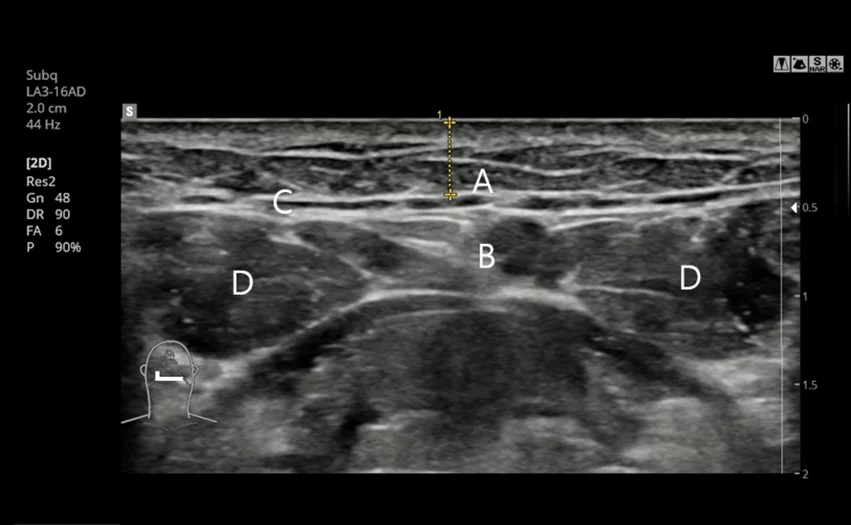

5. 手术前通过 CT 与超声进行精密个性化诊断

通过 CT 影像与超声检查

精确分析脂肪层位置与大小,

必要时可进行更加细致、个性化的脂肪层去除手术。